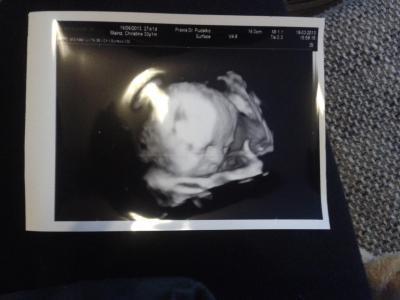

Bin ein wenig enttäuscht vom 3D Ultraschall, er wollt sich gar nicht zeigen und hatte ein Beinchen überm Kopf die Arme ins Gesicht eingekuschelt und die Nabelschnur und alles andere im Gesicht. Vielleicht klappt es ja besser beim nächsten Mal, wenn er dann nicht schon zu groß ist :-(

Bild zu 3D - Schwanger - wer noch? Rund um die Schwangerschaft

Ist doch total süß das Foto, weiß gar net was du hast!?!? lg Manu

Ist doch total schön das Foto man sieht doch schon richtig viel . LG Sabrina